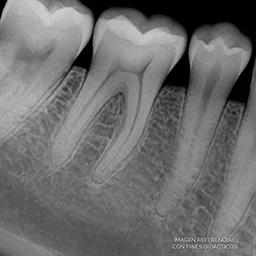

Ejemplo Radiografía Periapical

imagen referencial con fines didácticos

La radiografía periapical (o retroalveolar) es una técnica intraoral que muestra con detalle uno o varios dientes completos, desde la corona hasta el ápice y las estructuras circundantes. Es fundamental para detectar caries profundas, enfermedades periodontales, fracturas, infecciones o lesiones periapicales.